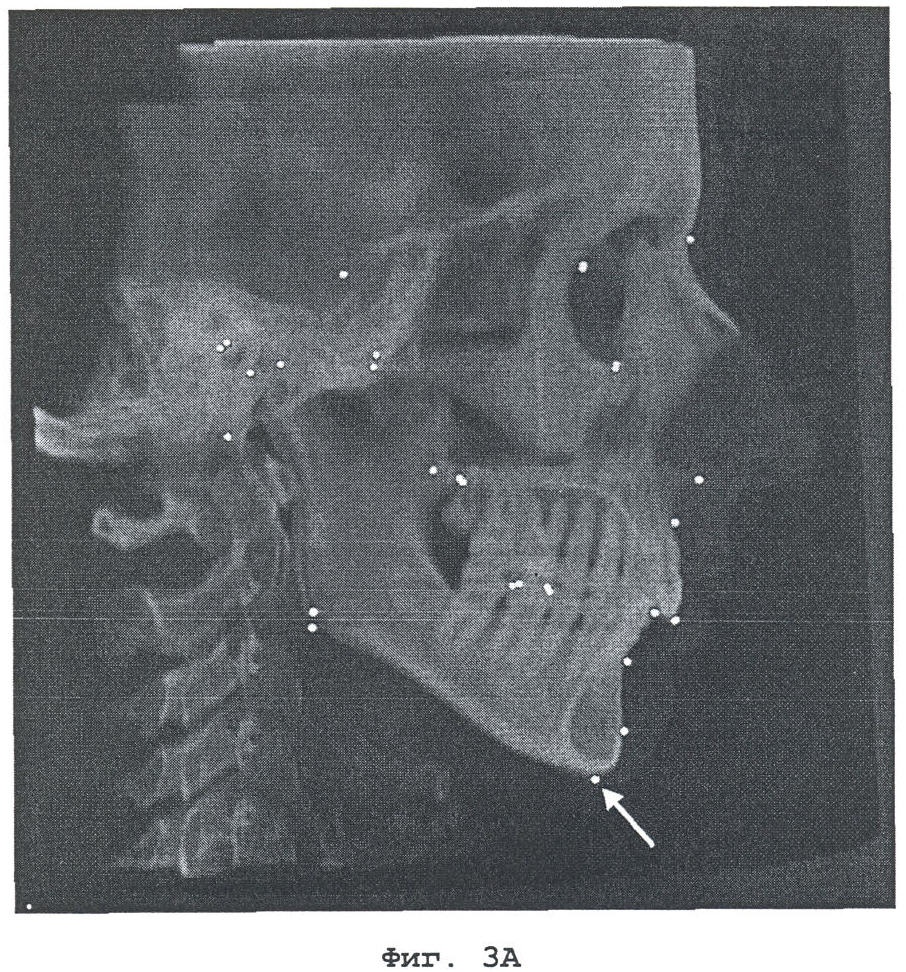

На фиг.3А и 3В показано задание анатомических ориентиров. Для точного определения точек используются как цефалограмма в боковой проекции, так и трехмерная модель костной поверхности.

На следующем этапе задают анатомические ориентиры для анализа. Ориентиры представляют собой анатомические точки на твердых или мягких тканях. Они могут быть указаны на модели поверхности или на двумерной цефалограмме (см. фиг.3). Выбранные анатомические точки могут определять анатомическую плоскость, которая должна рассматриваться в качестве одного из анатомических ориентиров.

При подготовке к репозиции костного фрагмента можно получить дополнительную полезную информацию с помощью описанного выше трехмерного цефалометрического анализа (фиг.5). Имея такую информацию, пользователь (как правило, хирург) может виртуально осуществлять репозицию костных фрагментов. В качестве примера на фиг.6 приведен результат виртуальной репозиции верхней челюсти. Возможно моделирование различных типов поступательного перемещения и поворота относительно ориентиров с использованием компьютеризованной системы планирования. Так, например, поворот вокруг некоторой оси или поступательное перемещение вдоль некоторого направления могут быть определены как пересечение двух плоскостей или как перпендикулярные к некоторой плоскости, либо могут быть заданы двумя ориентирами.